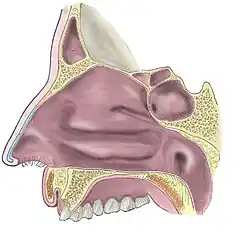

носова порожнина

носова порожнина

носова́ порожни́на • (nosová porožnýna) f inan (genitive носово́ї порожни́ни, nominative plural носові́ порожни́ни, genitive plural носови́х порожни́н)